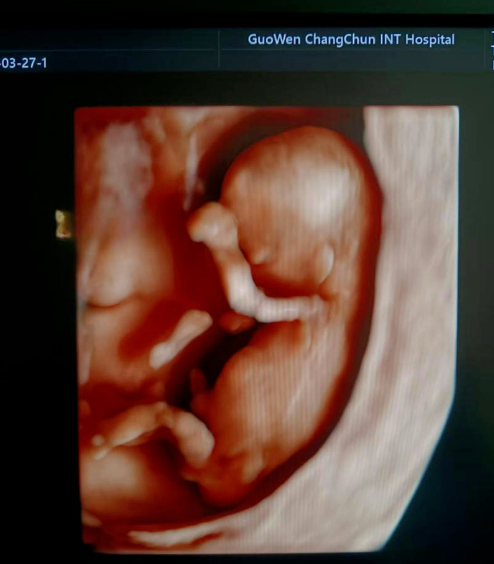

寶媽看過來! 胎兒NT彩超免費檢查長春國文醫(yī)院支持國家優(yōu)生優(yōu)育政策,回饋寶媽,NT彩超檢查免費。那么,什么是NT檢查呢?

NT 檢查是一種在孕期進行的重要檢查項目,全稱為頸項透明層檢查,以下是關于它的詳細介紹:

通常在懷孕 11 周 - 13 周 + 6 天之間進行。這個時期胎兒大小適中,頸項透明層的顯示較為清晰,測量結果也相對準確,能更好地發(fā)揮 NT 檢查對胎兒異常的篩查作用。

超聲檢查,孕婦無需空腹。檢查時,超聲醫(yī)生會使用超聲儀器對胎兒頸部進行仔細觀察和測量。通過超聲探頭可以清晰地看到胎兒在子宮內(nèi)的情況,重點測量胎兒頸項部皮下無回聲透明層最厚的部位,測量值即為 NT 值。正常胎兒 NT 值一般不超過 2.5mm。